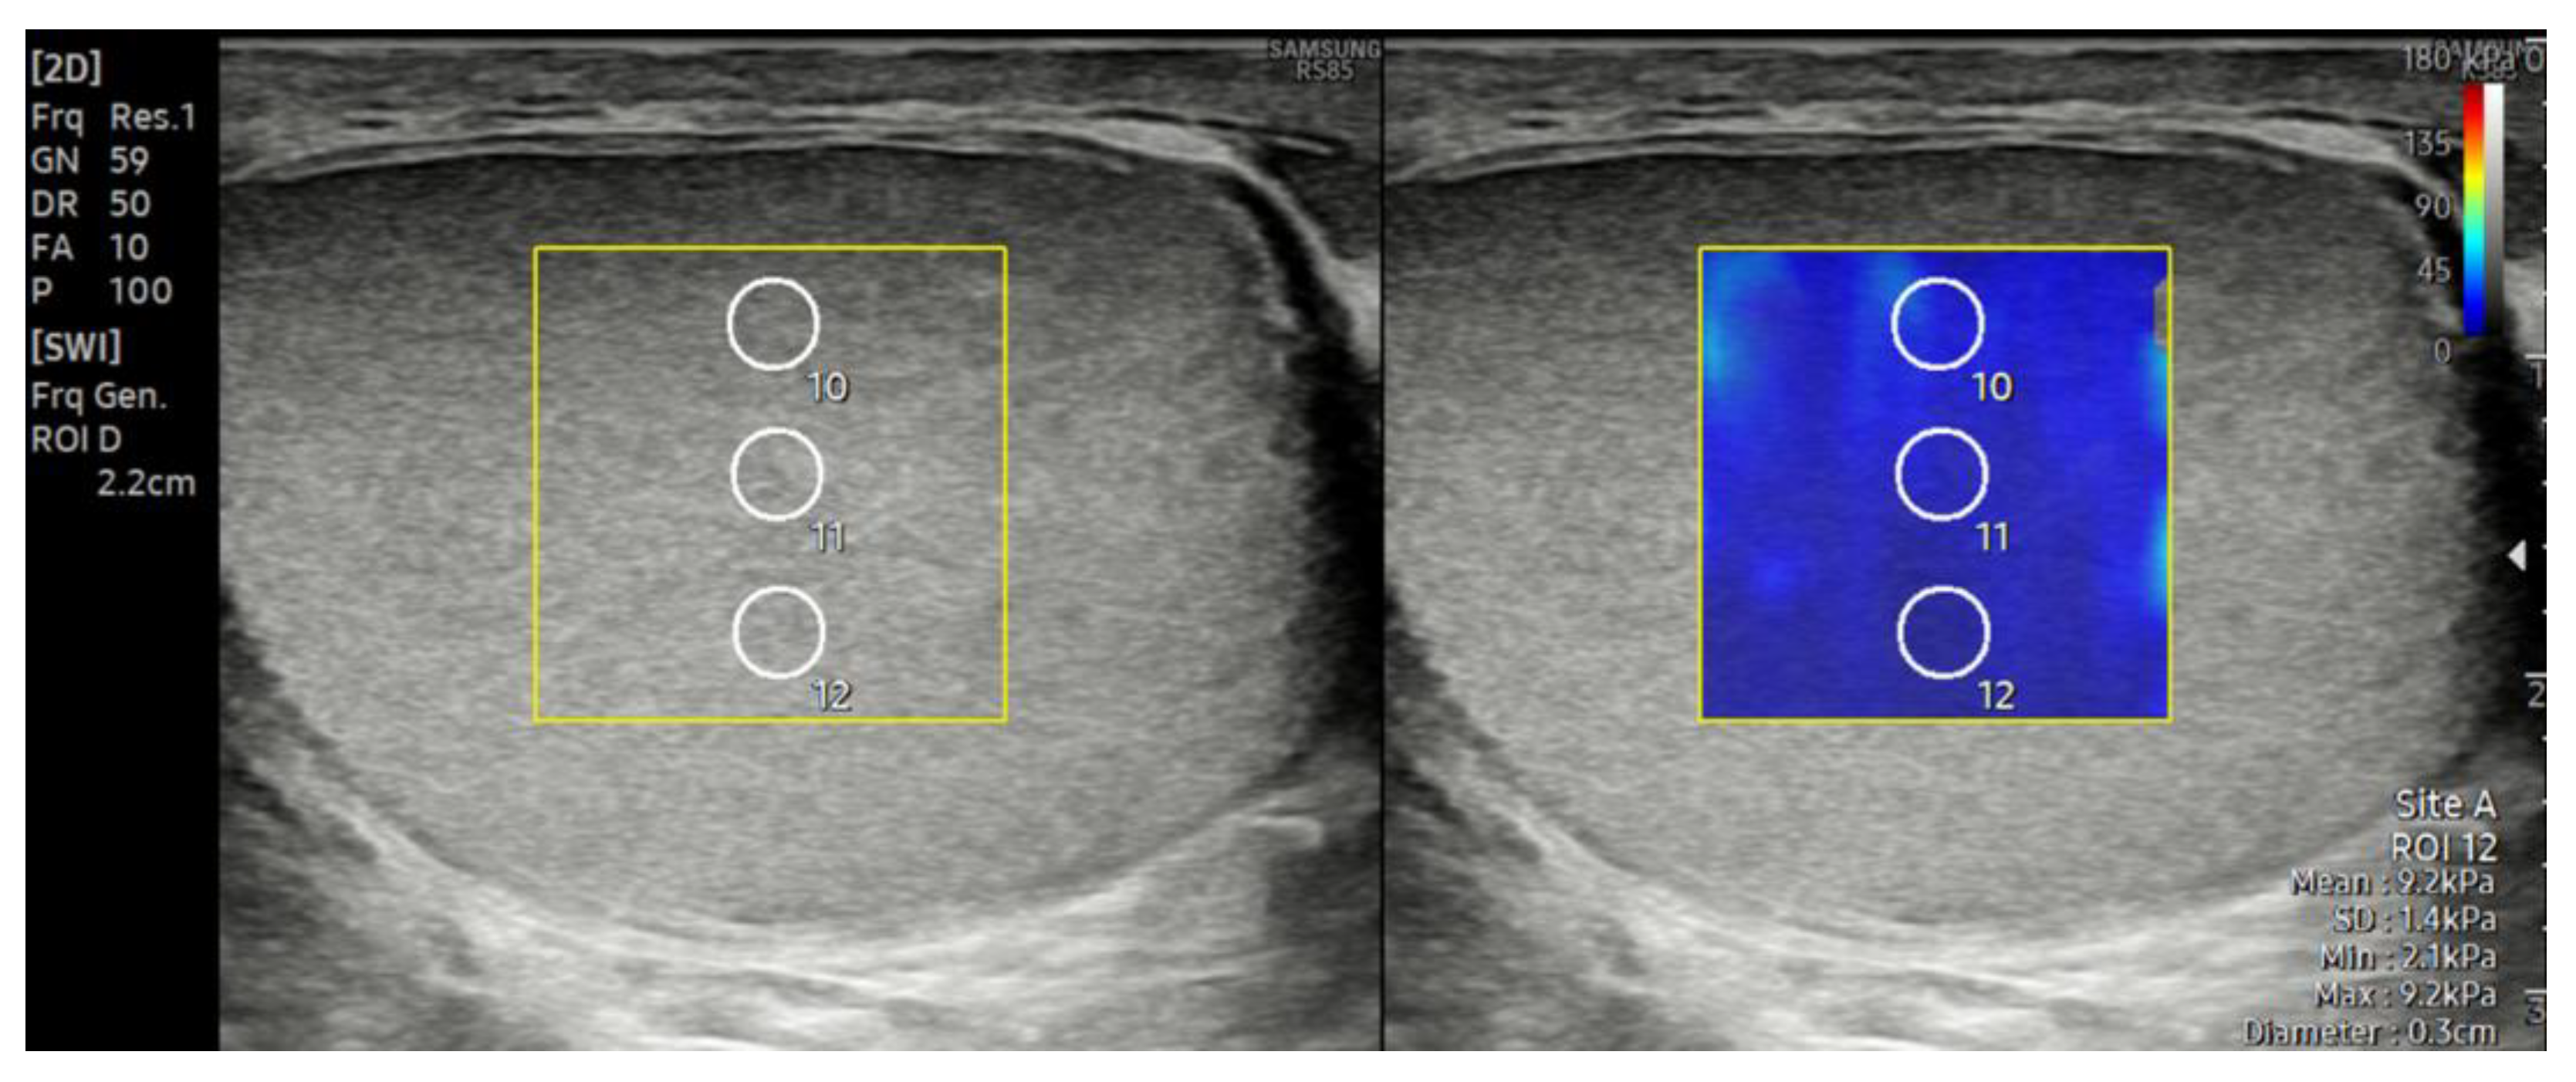

2.2. Ultrasonography and Shear Wave Elastography Examination